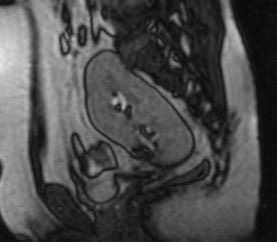

МРТ почек. Сагиттальная Т1-ВИ. Тазовое расположение почки.